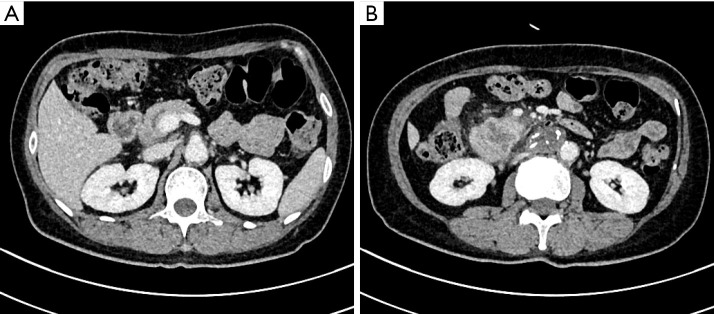

Case description: This report describes a 59-year-old female patient who underwent radical pancreaticoduodenectomy for pancreatic ductal adenocarcinoma (T2N0M0). On the 8th postoperative day, she developed back pain, followed by a sudden increase in body temperature, elevated inflammatory markers, and a significant increase in amylase levels in the drainage fluid. Enhanced abdominal computed tomography revealed that one side of the pancreatic duct support tube had penetrated the abdominal cavity, resulting in posterior peritoneal effusion. Emergency removal of the support tube and repair of the intestinal perforation were performed. The patient had an uneventful recovery after surgery and was discharged on day 20 following the second operation.